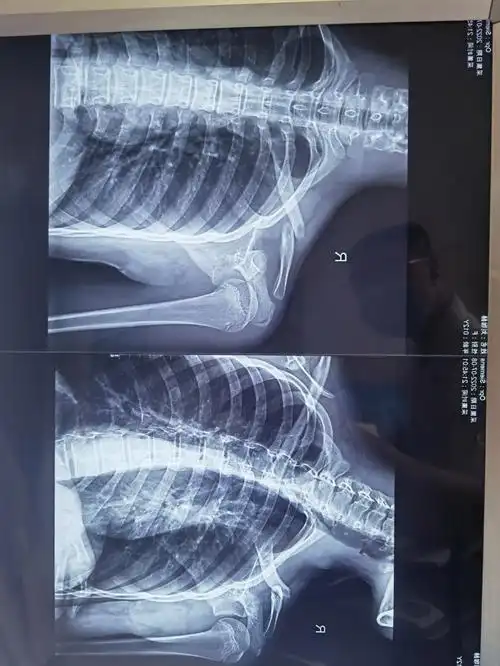

小姑娘12岁锁骨骨折第三张是术后的皮肤